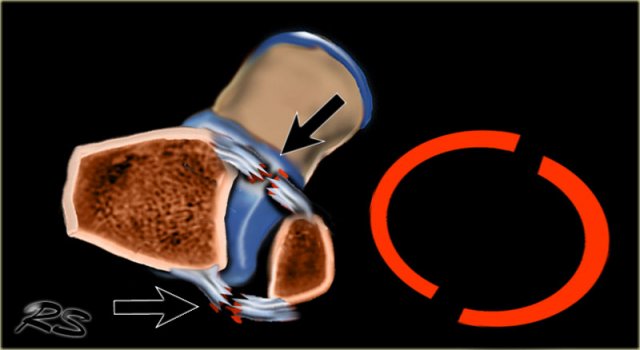

Ring of stability in the coronal plane Ring of stability in the coronal plane

Stability

The ankle can be thought of as a ring in which bones as well as ligaments play an equally important role in the maintenance of joint stability.

If the ring is broken in one place the ring remains stable.

When it is broken in two places, the ring is unstable and may dislocate.

Now anyone can figure out, that an ankle is unstable when both the medial and the lateral malleoli are fractured.

It becomes more problematic when there is a combination of a fracture and a ligamentous rupture, because the ligamentous rupture is not detectable on the X-ray.

In some fractures there may even be a proximal fibular fracture - which is not visible on the ankle radiographs - in combination with ligamentous ruptures at the level of the ankle.

It is important to realize that in these cases the radiographs of the ankle may be normal, while there still is an unstable ankle injury.

Ring of stability in the axial plane Ring of stability in the axial plane

There is also an ring of stability in the axial plane.

When the anterior and posterior syndesmosis rupture or avulse, then the ankle joint is also unstable.

There are many combinations of avulsion fractures and ligamentous ruptures that can produce an unstable ring in the axial plane.